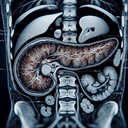

МРТ органів черевної порожнини

Магнітно-резонансна томографія (МРТ) органів черевної порожнини - це неінвазивний діагностичний метод, який використовує магнітне поле та радіохвилі для створення детальних зображень внутрішніх органів і структур. ### Коли проводиться МРТ черевної порожнини: 1. **Оцінка стану органів**: Наприклад, печінка, жовчний міхур, підшлункова залоза, селезінка, нирки...